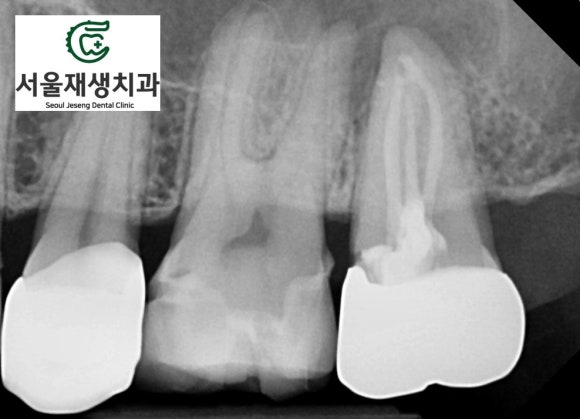

치료를 마무리합시다.

신경치료의 마지막 단계 + 크라운 만들기

![[재신경치료] 예전에 신경치료 한 치아가 갑자기 붓고 아파요! (현미경 신경치료, 서울재생치과) 관련 이미지 12](https://pub-9f2bb3498faf4d1d8714b41df24753e3.r2.dev/content/clinics/archive/nqmm0udu86/naver_blog/honeybeevuvu/assets/by_hash/3b029b4c4d658a781d19c49f6166c4e6d343df7f1e223ddeb3a9de4d9f0f10e9.jpg)

꽉꽉, 꽉꽉.

총 4개의 신경을 깨끗하게 밀봉합니다.

![[재신경치료] 예전에 신경치료 한 치아가 갑자기 붓고 아파요! (현미경 신경치료, 서울재생치과) 관련 이미지 13](https://pub-9f2bb3498faf4d1d8714b41df24753e3.r2.dev/content/clinics/archive/nqmm0udu86/naver_blog/honeybeevuvu/assets/by_hash/7b559e83048ebe63b38c6b38a68563504d2f6f2041602c0f88efdcaf88c8c89c.jpg)

겉으로는 도자기색상,

안쪽으로는 튼튼한 금속을 가진

PFM 크라운입니다.